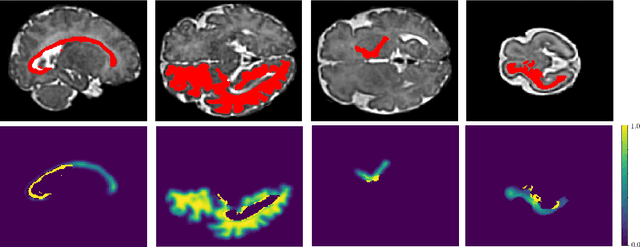

Abstract:Fetal cortical plate segmentation is essential in quantitative analysis of fetal brain maturation and cortical folding. Manual segmentation of the cortical plate, or manual refinement of automatic segmentations is tedious and time consuming, and automatic segmentation of the cortical plate is challenged by the relatively low resolution of the reconstructed fetal brain MRI scans compared to the thin structure of the cortical plate, partial voluming, and the wide range of variations in the morphology of the cortical plate as the brain matures during gestation. To reduce the burden of manual refinement of segmentations, we have developed a new and powerful deep learning segmentation method that exploits new deep attentive modules with mixed kernel convolutions within a fully convolutional neural network architecture that utilizes deep supervision and residual connections. Quantitative evaluation based on several performance measures and expert evaluations show that our method outperformed several state-of-the-art deep models for segmentation, as well as a state-of-the-art multi-atlas segmentation technique. In particular, we achieved average Dice similarity coefficient of 0.87, average Hausdroff distance of 0.96mm, and average symmetric surface difference of 0.28mm in cortical plate segmentation on reconstructed fetal brain MRI scans of fetuses scanned in the gestational age range of 16 to 39 weeks. By generating accurate cortical plate segmentations in less than 2 minutes, our method can facilitate and accelerate large-scale studies on normal and altered fetal brain cortical maturation and folding.